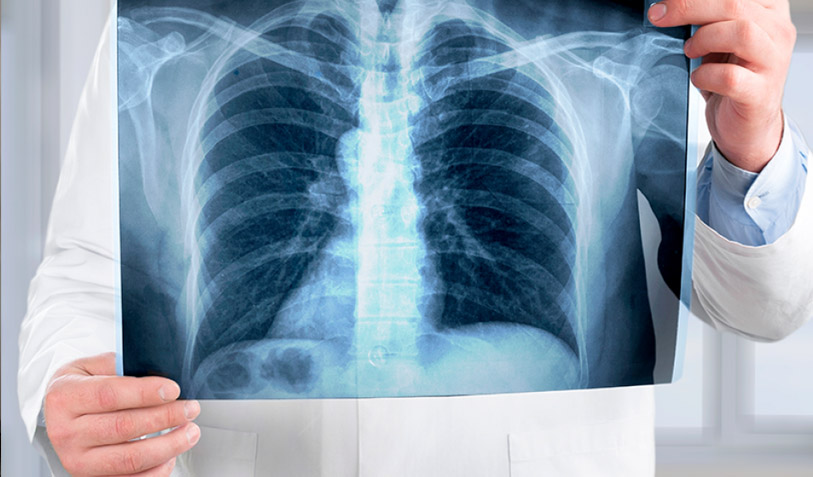

Gracias a la radiología es posible tratar fracturas, colocar prótesis según las necesidades de cada paciente, monitorear el desarrollo de los fetos y obtener imágenes precisas del cerebro, todo ello sin recurrir a cirugías ni procedimientos invasivos que generen dolor o riesgos mayores.

La fecha se eligió en honor al descubrimiento de los rayos X por Wilhelm Conrad Roentgen en 1895, quien observó un efecto fluorescente al trabajar con rayos catódicos. A partir de ese hallazgo, se comprendió que estos rayos permitían visualizar el interior del cuerpo humano, y tan solo tres meses después ya se utilizaban radiografías en hospitales importantes.